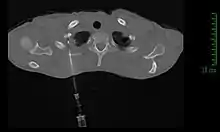

La méthode de diagnostic la plus précise est la ponction percutanée trans-thoracique par ponction à l’aiguille, sous contrôle scanner, qui présente un rendement de 95 %[11],[21]. En cas d'échec, il est possible de réaliser une biopsie chirurgicale par thoracoscopie ou thoracotomie[11].

La fibroscopie bronchique est souvent peu contributive ; la localisation très périphérique de la tumeur la rend en effet inaccessible techniquement. La fibroscopie ne permet ainsi de réaliser des biopsies de la tumeur que dans environ 20 % des cas[21],[11].